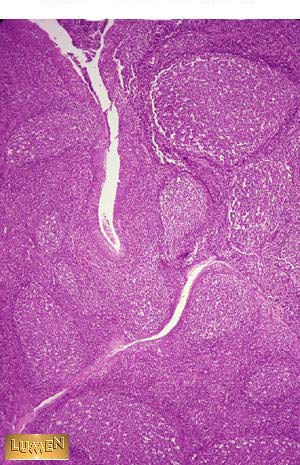

Palatine Tonsil